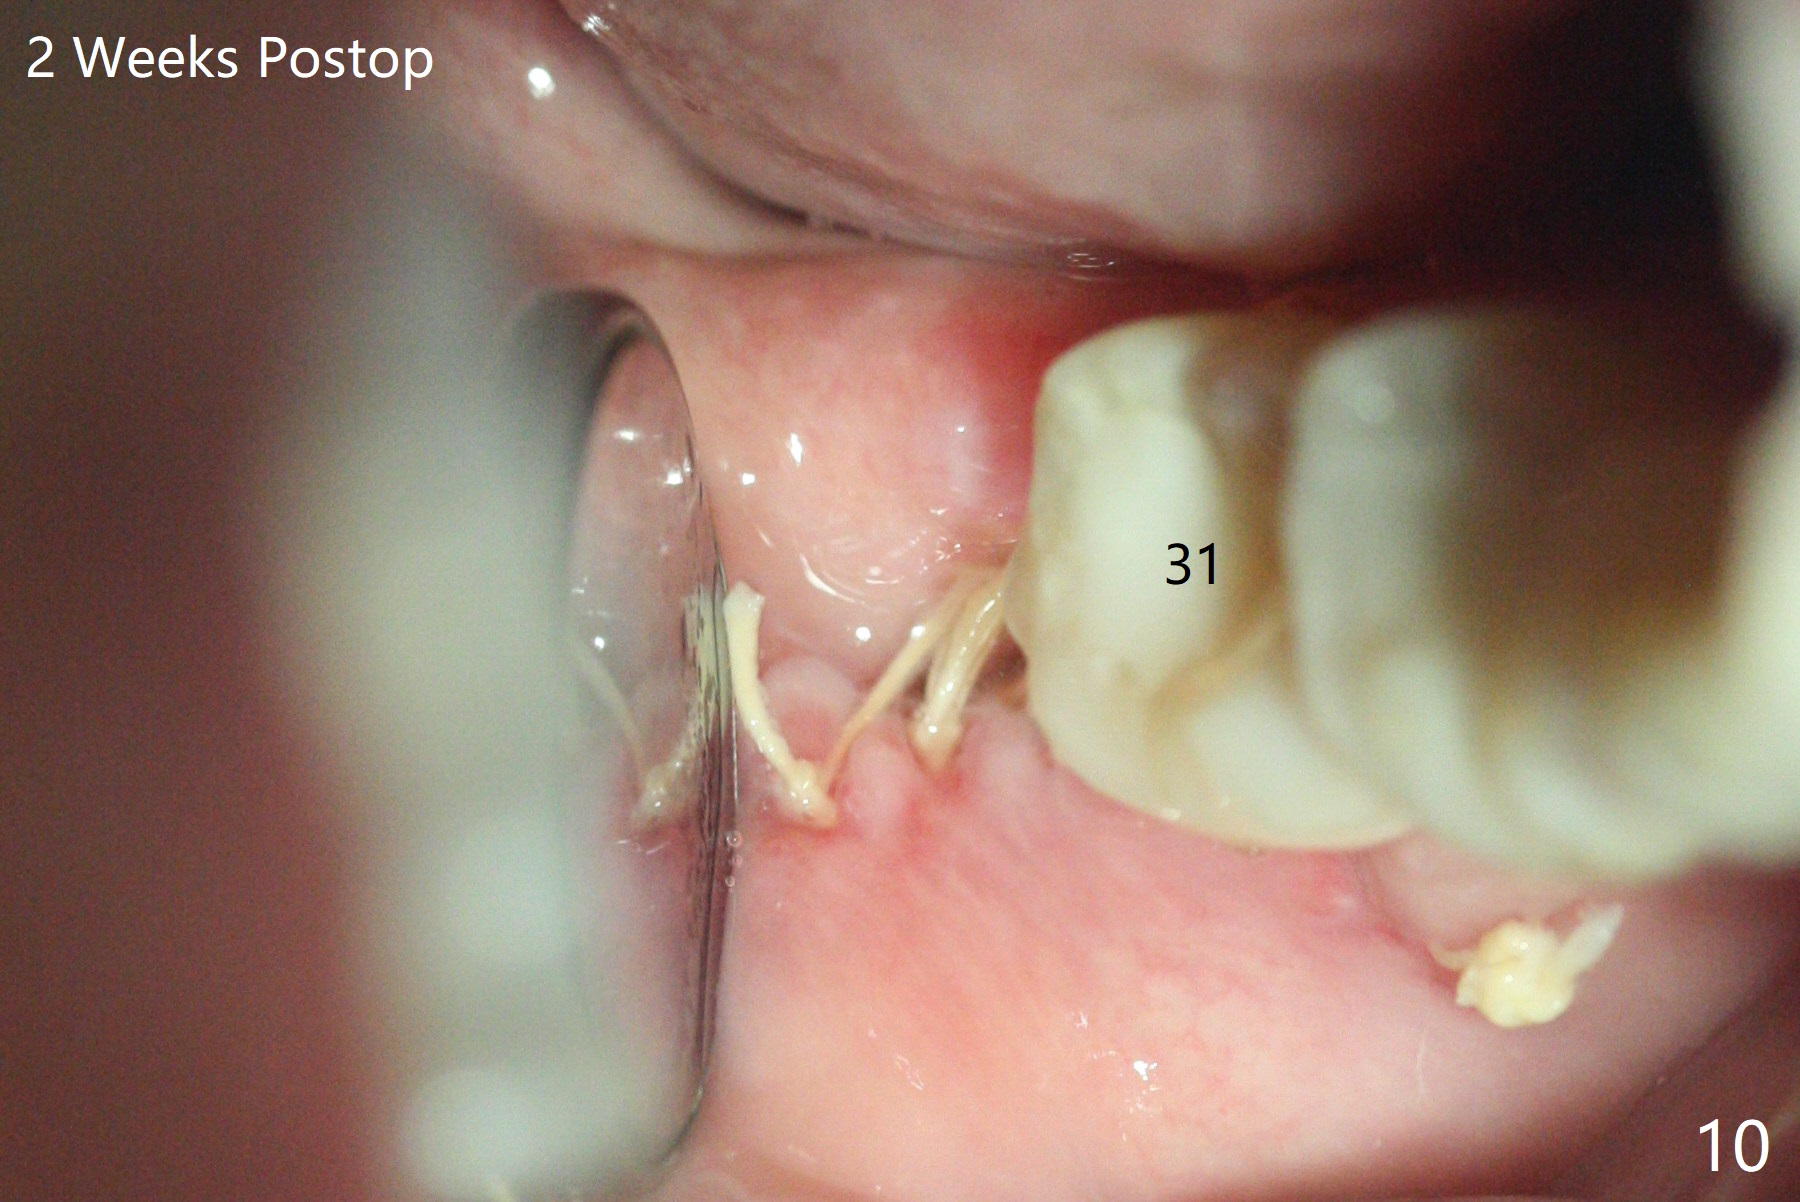

A 37-year-old woman requests extraction of the 3rd molars and orthodontic retreatment (Fig.1). Since the bone between #17 and 18 is thin and short (Fig.2 black *), bone graft is needed after #17 extraction. But the apical infection at #18 (Fig.2 white *) may affect graft survival. The patient agrees to have RCT retreatment done (Fig.3 white curved lines) before extraction (black area). The apical granulation tissue can be removed (Fig.4 red area) prior to bone graft (Augma). The latter will be also placed at #17 as a control. After endodontic consultation, the patient does not want RCT retreatment. She would like to have the 3rd molars extracted first and #18 removed if needed. After #17 extraction (Fig.5), apicoectomy will be performed at #18 (Fig.6 (white outline: surgical bur, use non-torque handpiece)). Following curettage of the apical lesion at #18 (Fig.7), bone graft will be placed (Fig.8 red circles). In fact the patient insists upon #1, 16, 17, and 32 extraction. After extraction, allograft (Fig.9 A (Ossogen, Mineralized Cort/Can (30%/70%), .25-1.0 mm) is placed in the mesioapical of the sockets of #17 and 32, while Osteogen Plug (O) and BioXclude in the distocoronal one (4-0 PGA suture). There is minimal bone between the 2nd and 3rd molars (black arrowheads). The allograft is intentionally pushed into #18 apical defect after enucleation (white arrowhead). The sockets are slightly open, although sutures are in place 2 weeks postop (Fig.10,11). It is unknown whether the bone graft is partially dislodged or not.